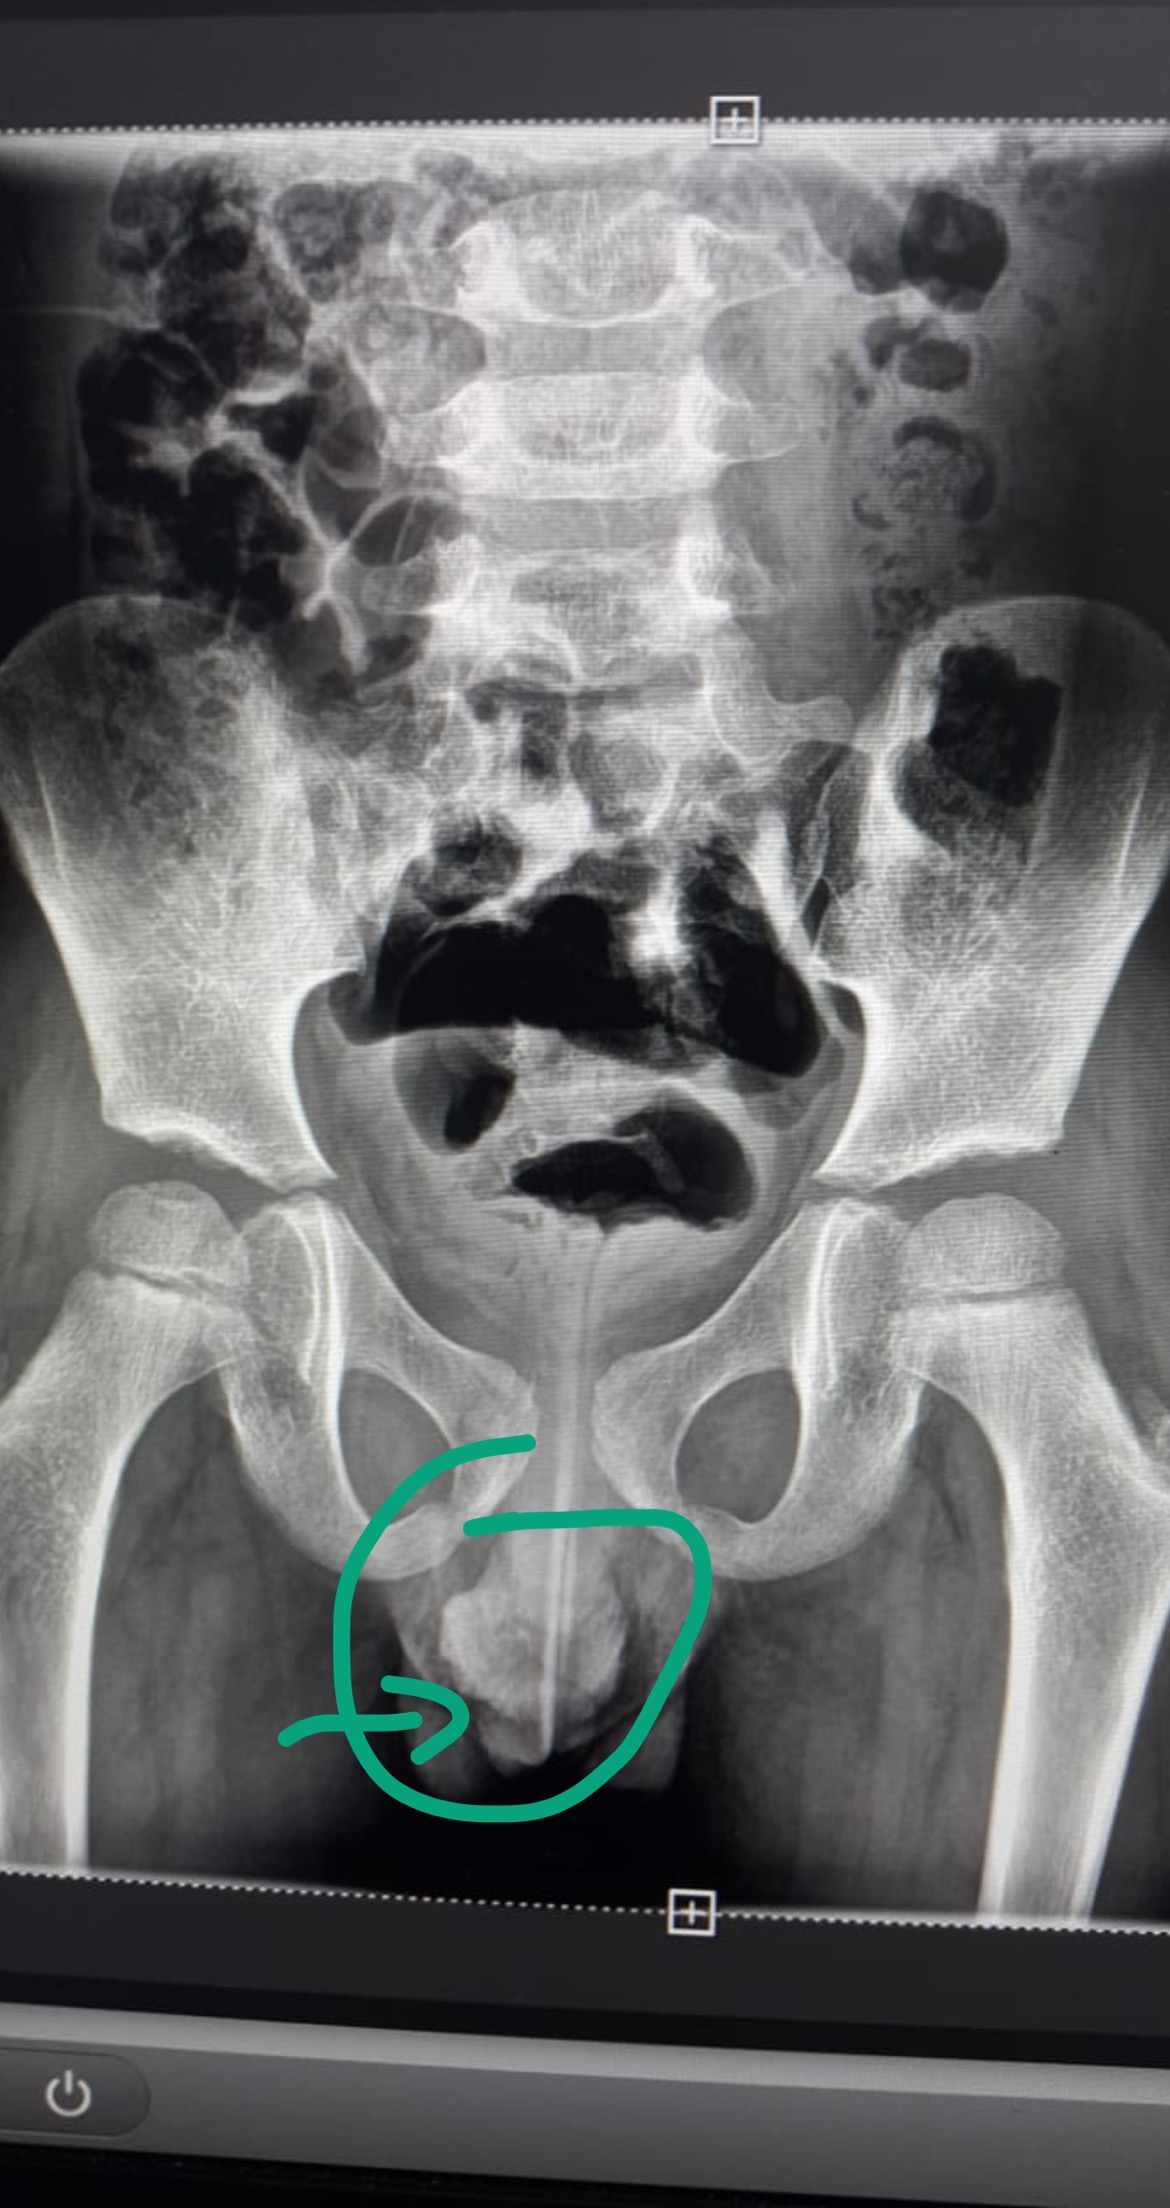

لدا طفلي انتفاخ مؤقت في جلدة القضيب تكون لساعات قليلة ثم تختفي ما السبب مع العلم لاتوجد افرازت ولا احمرار ولا الم فقط انتفاخ في الجلدة اليمنى للقضيب

صورة مرفقة

شاهدت الصورة

و قد يكون سبب انتفاخ جلدة القلفة احد ما يلي :

- التحسس الجلدي

- الرض المتكرر بسبب ملابس ضيقة او ركوب الدراجة ...

- كيس ماء على الخصية

- فتق اربي متردد

- اسباب اخرى اقل احتمالا